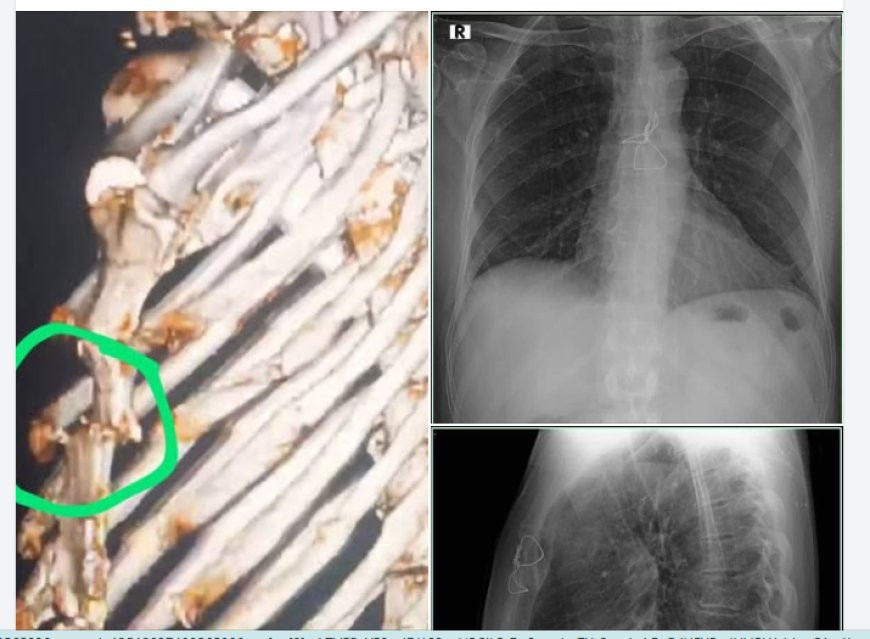

في إنجاز طبي جديد يُضاف إلى سجل النجاحات الطبية في حضرموت، نجح فريق جراحة الصدر في مستشفى حضرموت الحديث، بقيادة الدكتور يحيى باحميش – أخصائي أول جراحة الصدر، في إجراء عملية إصلاح وتثبيت كسر في عظمة القص لمريض ستيني من محافظة المهرة كان يعاني من آلام حادة وعدم استقرار في جدار الصدر نتيجة حادث سير مروري.

وأوضح الفريق الطبي أن العملية تضمنت تثبيت عظمة القص باستخدام أسلاك معدنية دقيقة من نوع (Stainless Steel Wire)، وهي تقنية متقدمة تُستخدم لضمان استعادة الشكل التشريحي واستقرار حركة الصدر وتحسين وظائف التنفس بعد الإصابات المعقدة.